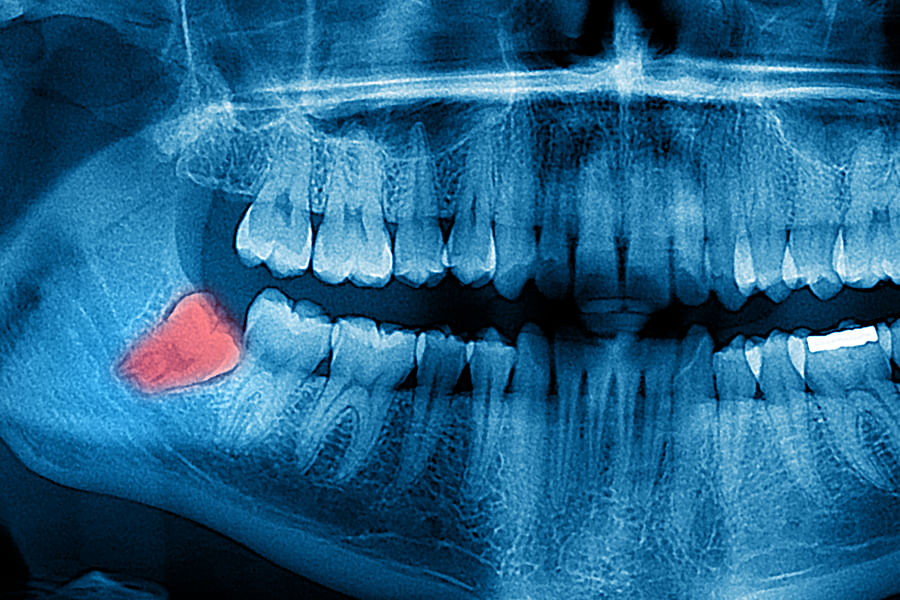

Dental X-rays are more than just tools for diagnosing cavities; they provide a comprehensive view of your oral health status. By allowing dentists to detect problems before they become severe, these images can save patients time, money, and discomfort in the long run. Early detection through modern imaging technology can reveal hidden decay between teeth, bone loss due to gum disease, or even cysts and tumors that are not visible during a standard exam.

- Impacted Teeth - Revealing teeth that are not properly erupting, such as wisdom teeth.

- Tumors - Spotting abnormal growths or cysts within the jawbone.

Despite the myths surrounding dental x-rays, they play an integral role in preventative dentistry. X-rays allow dentists to detect issues that are not visible during a standard oral exam. This includes early signs of decay between teeth, problems below the gum line, and changes in bone density that could indicate periodontal disease. By identifying these problems early, fundamental dental treatments can be administered promptly, saving patients from more extensive and costly procedures down the line.